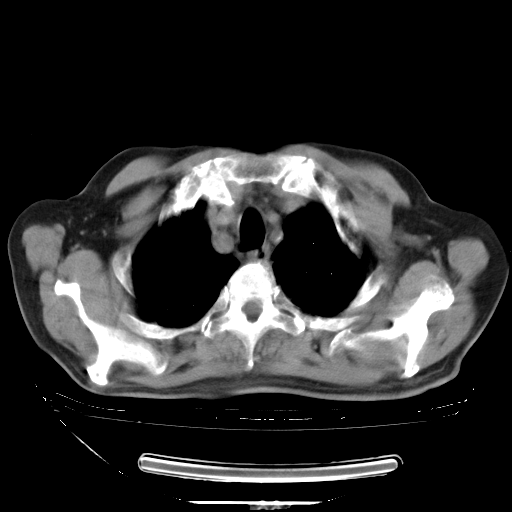

胸腹部CT,诊断意见:左上肺叶钙化灶、左侧胸膜局限性增厚并钙化、胆囊炎。描述部分肺组织呈磨玻璃样改变。

今天复查肺部CT,发现双肺广泛磨玻璃样改变。所以我把3月19日和5月9日相隔50天的肺部CT上传。请大家会诊。

5月9日肺部CT(在4月27日齐鲁医院肺部CT描述部分肺组织磨玻璃样改变,12天后肺组织广泛磨玻璃样改变)

大致读了系列胸部CT:纵隔窗无明显异常,肺窗:从4、27至今:主要是双肺中下野外带可见毛玻璃样改变,目前处于急性肺泡炎阶段,至于原因考虑1、结替组织或胶原血管性疾病所致?2、恶性疾病如恶组在肺部所致的表现或细支气管肺泡癌?3、药物或其它原因如肺蛋白沉着症所致肺泡炎目前不太可能?总之,明天就去请我院的呼吸科、感染科、血液科和临免专家会诊哈。